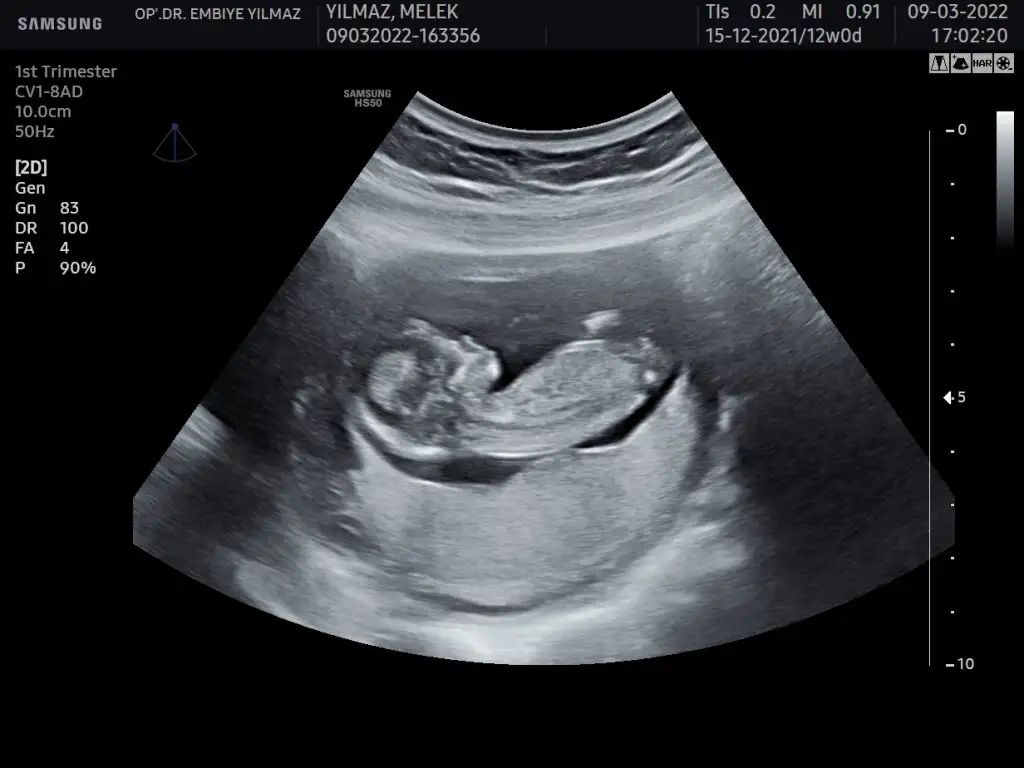

Ben bişey anlayamadım nuba göre benim ne oluyor acabaCumartesi cinsiyet öğreneceğim o yüzden bütün teorileri araştırırken bu karşıma çıktı bana mantıklı geldi gibişöyle ki omurgadan popoya doğru giden çizgi sonda yukarı doğru çıkıyorsa erkek, düz gidiyorsa kız oluyormuş fotoğraf ekleyeceğim orda daha ayrıntılı gösteriyor

Dr da öyle dedi emin olamadı alttan bakınca da kıza benziyor dediAyy maşallah ne güzel çıkmışsanki şu işaretlediğim yerde yukarı doğru bir çıkıntı varmış gibi geldi bana Öyle olunca da erkek deniyor ama bilemiyorum tamamen benim yorumum